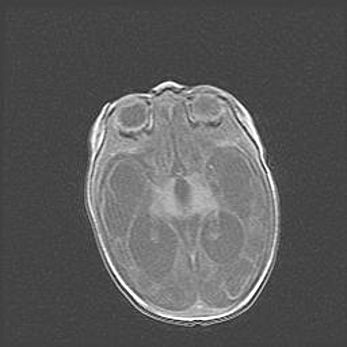

Подострая гематома правой гемисферы мозжечка.

Наружная гидроцефалия.

Возраст: 15 дней

Вес: 3100 г

Пол: женский

Окружность головы: 37 см

Срок гестации: 35-36 недель

При открытой наружной форме гидроцефалии у новорожденных расширяются и переполняются субарахноидные пространства.

Кровоизлияния в мозжечок имеют две клинико-анатомические формы: полушарные гематомы и кровоизлияния в червь.

К появлению этой патологии может привести: повреждения головного мозга, возникающие в результате асфиксии и гипоксии плода при беременности, или травмы во время родов. Редко гематома мозжечка может быть результатом первичной коагулопатии и сосудистой мальформации, диссеминированном внутрисосудистом свертывании, изоиммунной тромбоцитопении.